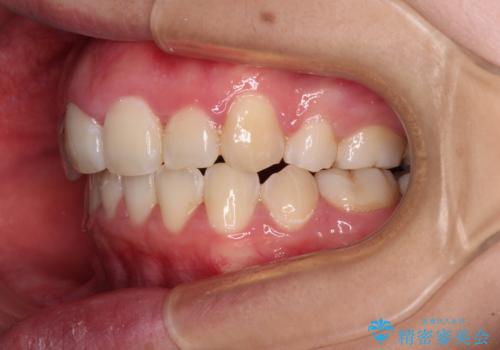

骨格的なズレをカムフラージュ 抜歯矯正で咬み合わせを改善

- 骨格的な咬み合わせのズレ、前歯のデコボコとクロスバイトを気にして来院された患者様です。

口元の突出感が若干あり口が閉じにくく、デコボコが強いため、上下左右の小臼歯計4歯を抜歯し、ワイヤー装置による矯正治療を行うこととしました。